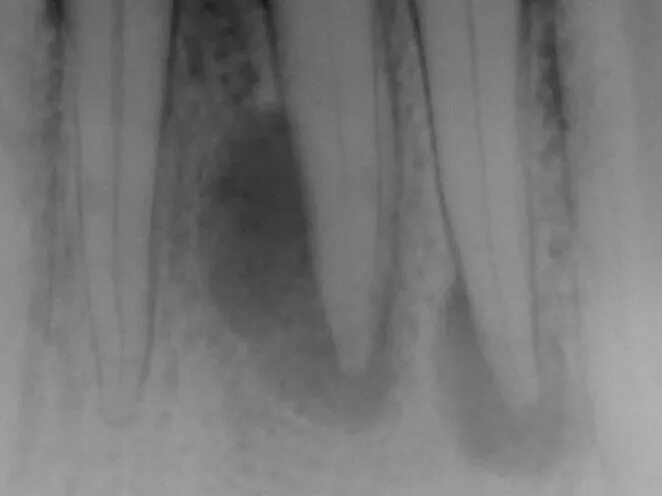

Киста зуба что это